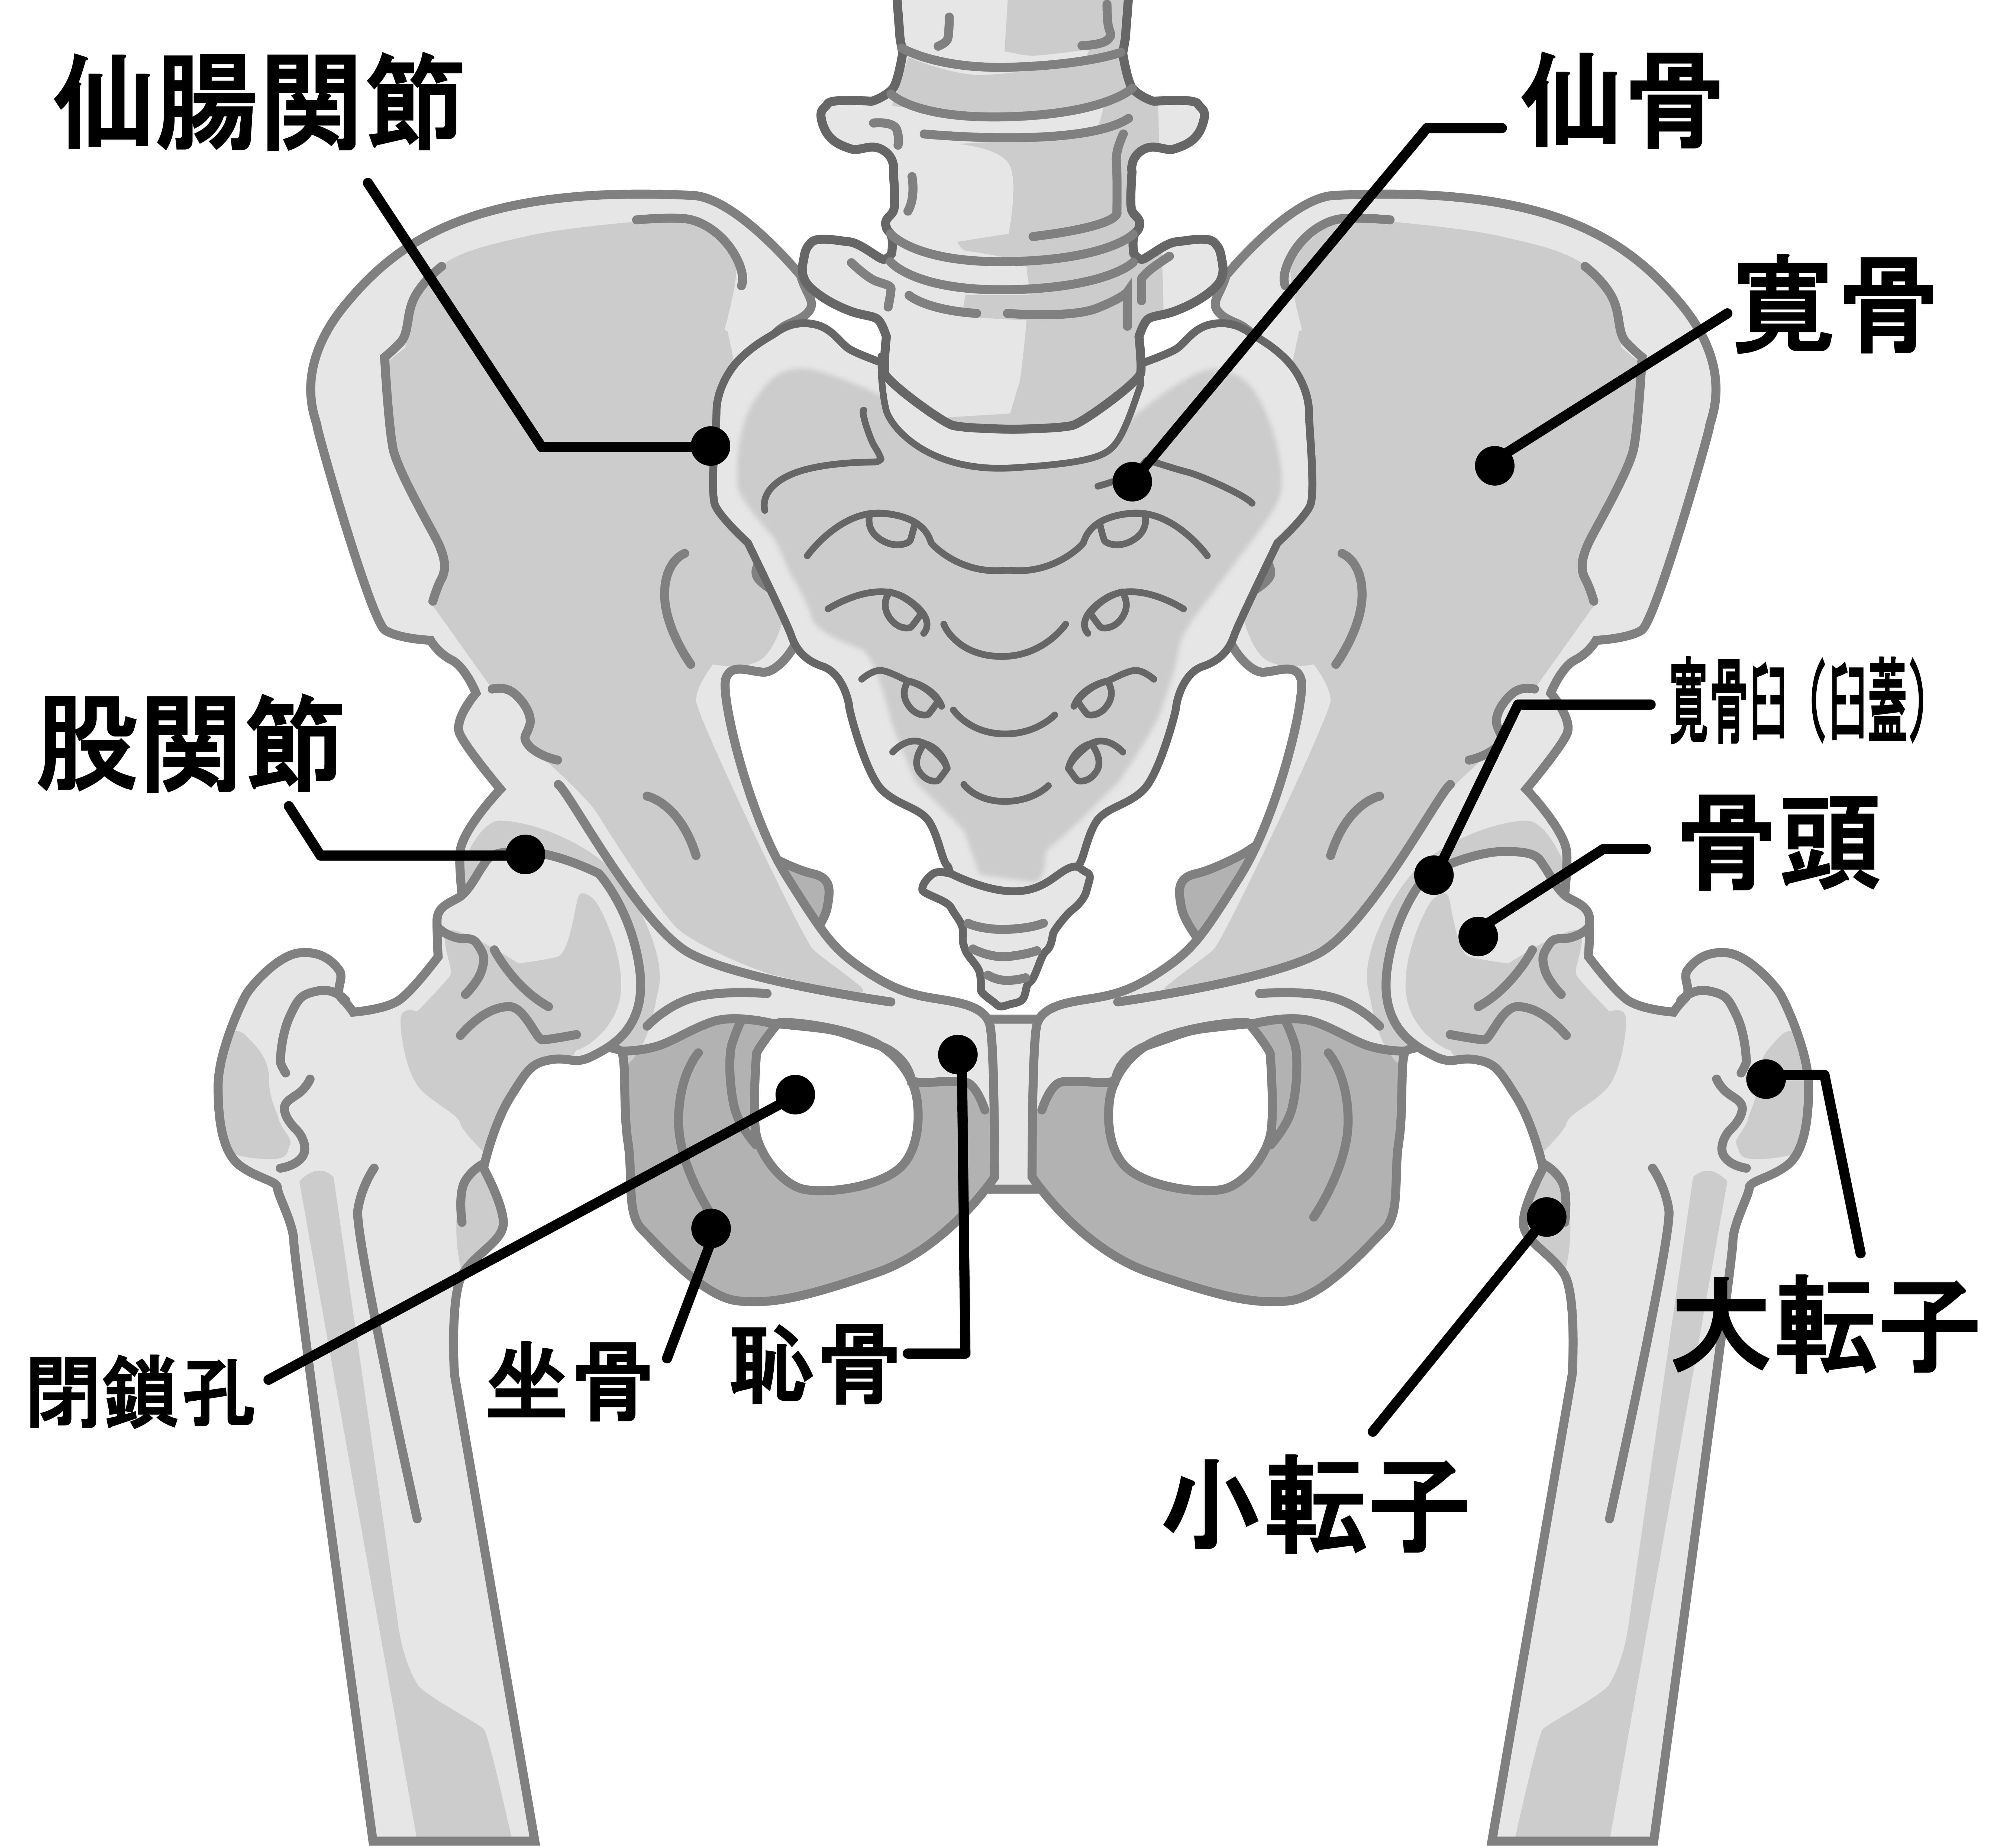

人工股関節置換術の手術と同様に

筋肉を切らないアプローチを用いて人工膝関節置換術を行っています。

内側広筋を切らないアプローチ(Subvastus approach)です。